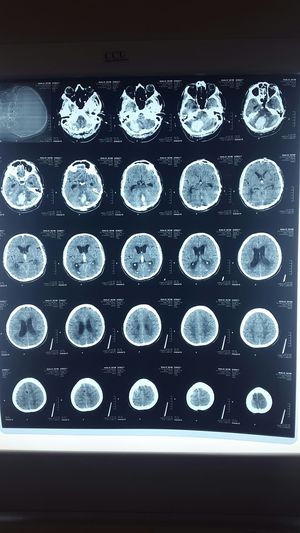

What is diagnose ?

Posterior fossa ICH with ventricular extension with hydrocephalus